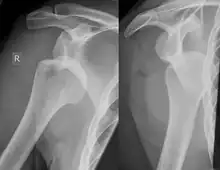

Diagnosis can be suspected by history and physical examination which is usually followed by imaging. Because of the mechanism of injury, apprehension of anterior dislocation is common with provocative maneuvers. Hill–Sachs lesions have been classified as "engaging" or "non-engaging", with engaging lesions defined by the ability of the glenoid to sublux into the humeral head defect during abduction and external rotation. Engaging dislocations have a higher risk of recurrent anterior dislocation, and their presence can help guide surgical management.[2] Imaging diagnosis conventionally begins with plain film radiography. Generally, anteroposterior (AP) radiographs of the shoulder with the arm in internal rotation offer the best yield while axillary views and AP radiographs with external rotation tend to obscure the defect. However, pain and tenderness in the injured joint make appropriate positioning difficult and in a recent study of plain film x-ray for Hill–Sachs lesions, the sensitivity was only about 20%. i.e. the finding was not visible on plain film x-ray about 80% of the time.[3]

The incidence of Hill–Sachs lesion is not known with certainty. It has been reported to be present in 40% to 90% of patients presenting with anterior shoulder instability, that is subluxation or dislocation.[8][9] In those who have recurrent events, it may be as high as 100%.[10] Its presence is a specific sign of dislocation and can thus be used as an indicator that dislocation has occurred even if the joint has since regained its normal alignment. Large, engaging Hill-Sachs fractures can contribute to shoulder instability and will often cause painful clicking, catching, or popping. The average depth of Hill–Sachs lesion has been reported as 4.1 mm.[11]